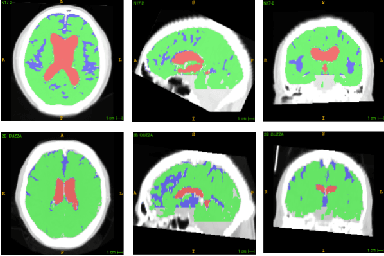

Abstract:Normal Pressure Hydrocephalus (NPH) is one of the few reversible forms of dementia. Due to their low cost and versatility, Computed Tomography (CT) scans have long been used as an aid to help diagnose intracerebral anomalies such as NPH. However, because CT imaging presents 2-dimensional slices of a 3-dimensional volume, recapitulating the ventricular space in 3-dimensions to facilitate the diagnosis of NPH poses numerous challenges such as head rotation and human error. As such, no well-defined and effective protocol currently exists for the analysis of CT scan-based ventricular, white matter and subarachnoid space volumes in the setting of NPH. The Evan's ratio, an approximation of the ratio of ventricle to brain volume using only one 2D slice of the scan, has been proposed but is not robust. Instead of manually measuring a 2-dimensional proxy for the ratio of ventricle volume to brain volume, this study proposes an automated method of calculating the brain volumes for better recognition of NPH from a radiological standpoint. The method first aligns the subject CT volume to a common space through an affine transformation, then uses a random forest classifier to mask relevant tissue types. A 3D morphological segmentation method is used to partition the brain volume, which in turn is used to train machine learning methods to classify the subjects into non-NPH vs. NPH based on volumetric information.